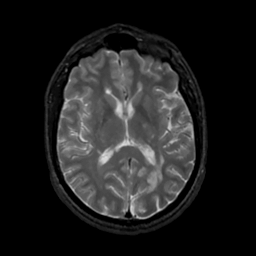

MR Study #7, March 24, 1991 -- Slice #27